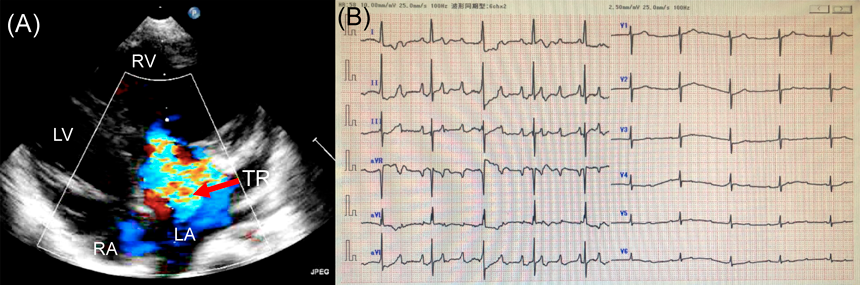

ペースメーカ植え込み後の心エコー検査:軽度TR(Fig. 2A).

Fig. 2 Echocardiography and angiography after a pacemaker implantation

(A) Four chamber view. (B) Anatomical left ventriculography. (C) Anatomical right ventriculography. LA, left atrium; LV, left ventricle; RA, right atrium; RV, right ventricle; TR, tricuspid regurgitation.

ペースメーカ植え込み後の心カテーテル検査:解剖学的左室拡張末期容積(LVEDV)68% of normal(Fig. 2B),解剖学的右室拡張末期容積(RVEDV)88% of normal(Fig. 2C).